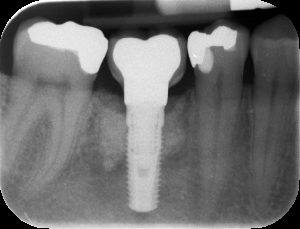

Künstliche Wurzel aus Titan

mit einer Krone zum Ersatz eines fehlenden Zahnes. |